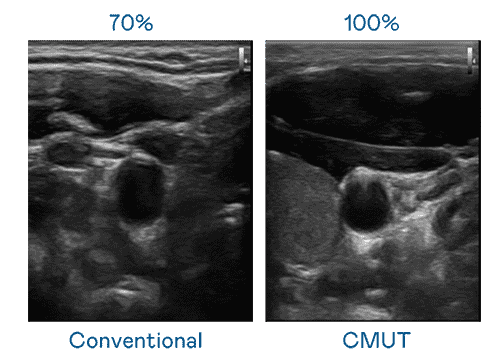

CMUT 技术是一种用电容式微机电元件来产生超音波讯号的技术。。。与传统 PZT 压电式技术相比,,CMUT 频宽增加 30%,,更宽频的超音波讯号让影像解析度大幅提升,,,,是实现高影像品质医疗超音波扫描、、促进精准医疗发展的关键技术。。

大频宽带来超清晰影像

超音波影像的解析度高低,,首先取决于探头能发出的讯号频宽。。。优游UB8 CMUT 可提供高清晰的超音波讯号,,,,提供高频宽、、、、高灵敏度、、影像纹理细节更高的超音波影像,,协助医护人员缩短影像判读时间及利用精准的医疗影像进行诊断。。。